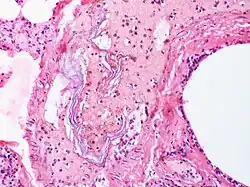

Sicher diagnostizieren kann man eine Fruchtwasserembolie erst post mortem im Rahmen einer Obduktion, indem man histologisch Fruchtwasser oder korpuskuläre Anteile in den Kapillaren der Lunge nachweist. Dies dient oftmals auch dazu, vermutete Behandlungsfehler durch Ärzte und Hebammen auszuschließen.[25]

- Histologisches Bild der University of Utah